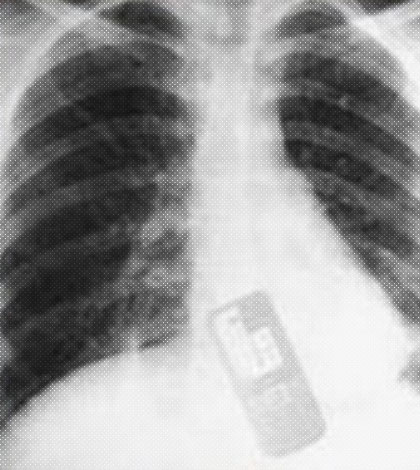

La joven fue llevada inmediatamente al centro médico más cercano, donde recibió los primeros auxilios y las medidas pertinentes para extraer el teléfono antes de que su buzón de mensajes se llene o comience a vibrar por un llamada entrante.

Los médicos se sorprendieron con el caso. Todos están ansiosos por saber que ocultaba Adriana en su teléfono